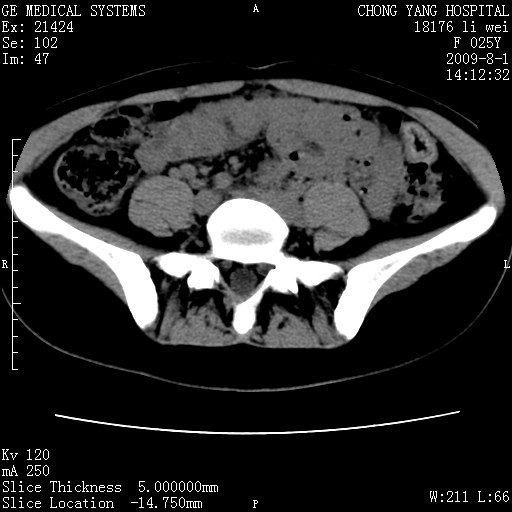

以下是引用pujunzhi在2009-8-1 20:23:00的发言:[br]胸椎旁及背部肌间良性病变,范围广,边界清,沿肌间生长,考虑淋巴管瘤、血管瘤,建议增强扫描。

以下是引用拾荒者在2009-12-30 21:45:00的发言:[br]ct21383:神经纤维瘤病( nf) [br] [br] 神经纤维瘤病。四肢都有,影响美观,四肢上的手术了。[br] [br] [br]谢谢!